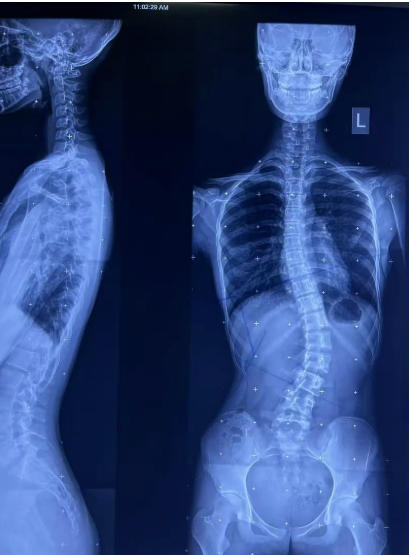

简单说,就是脊柱的一个或多个节段向侧方弯曲,形成带有弧度的异常形态,还常伴有椎体旋转。医学上定义为 10-18 岁青少年脊柱冠状面弯曲超过 10°,这种情况被称为 “青少年特发性脊柱侧弯”,也是最常见的类型。

确诊脊柱侧弯后,治疗方案主要根据 Cobb 角(X 线全脊柱片测量的侧弯角度)来定,分级治疗更科学:

10° 以下:无需特殊医疗干预,重点靠日常锻炼 + 姿势矫正,定期复查即可;11°-20°:配合保守治疗 + 矫正训练,坚持日常姿势矫正;21°-40°:在治疗基础上佩戴支具,定期调整支具参数;41° 以上:原则上需要手术治疗,避免侧弯进一步恶化影响心肺功能。